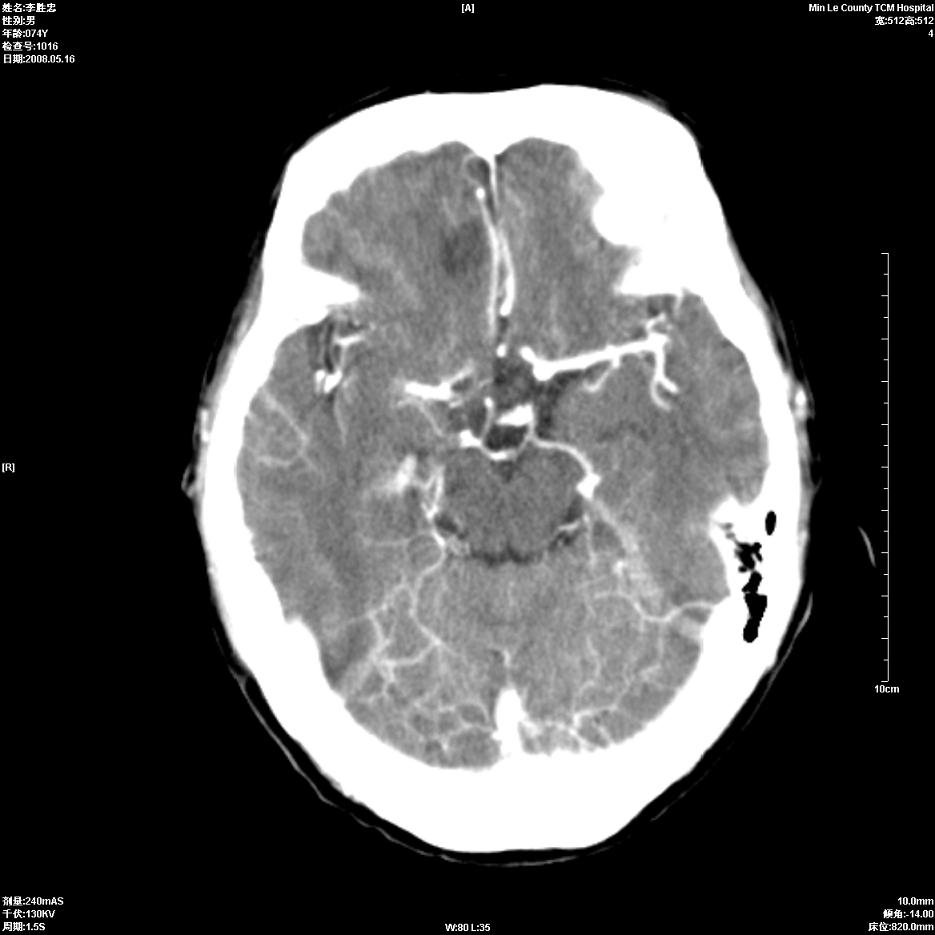

以下是引用深泽交通医院在2008-5-30 15:06:00的发言:[br]多发蛛网膜囊肿